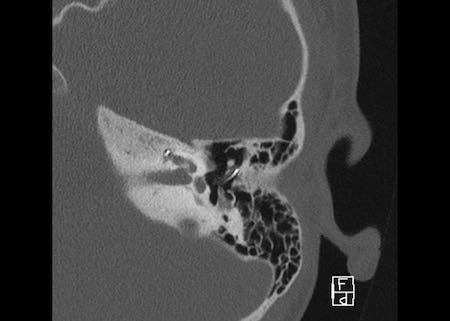

Bên trái là hình ảnh của một bé gái 2 tuổi.

Các hình ảnh từ kết quả chụp CT được thực hiện trước khi cấy ốc tai điện tử.

Quan sát thấy dị dạng nhẹ ở đỉnh ốc tai – không có sự phân tách giữa vòng thứ hai và vòng thứ ba, và trụ ốc tai xương vắng mặt.

Cống tiền đình bình thường.